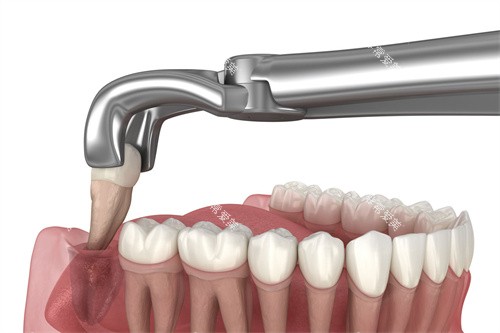

拔牙的价格受到多种因素的影响,如牙齿的位置、拔除的难易程度等。

普通拔牙

像松动牙、乳牙等较为容易拔除的牙齿,价格一般在50 - 150元。

这类拔牙操作相对简单,风险较低。

智齿拔除

智齿的生长情况较为复杂,拔除难度差异较大。

如果是正位智齿,拔除价格在200 - 500元左右。

但如果智齿是阻生的,如水平阻生、垂直阻生等,拔除过程较为复杂,可能需要切开牙龈、去除部分牙槽骨等操作,价格会明显升高,一般在500 - 1500元不等。